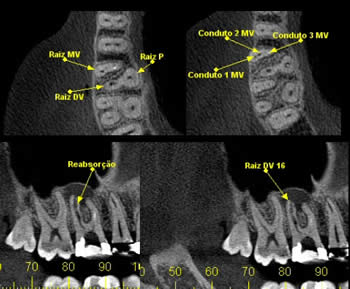

* Endodontia

Para verificar obturação dos canais radiculares, visualizar canais acessórios, perfurações, reabsorções e avaliação de fraturas radiculares.

CASO 6 - Reabsorção

Achado radiográfico, na radiografia periapical de rotina, nota-se área de menor densidade na distal cervical e alteração no contorno na mesial, e rarefação óssea periapical. Ao exame tomográfico pode-se observar o dente 11 com osteólise apical e área de reabsorção na distal e reabsorção por substituição na mesial.